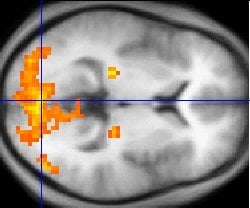

Using sophisticated imaging equipment at York Neuroimaging Centre (YNiC), the research found that the two neighbouring areas of the cortex, each about the size of a 5p coin and known as human visual field maps, process the different types of visual information independently.

Researchers used functional magnetic resonance imaging (fMRI) equipment at YNiC to pinpoint the two brain areas, which they subsequently targeted with magnetic fields that temporarily disrupt neural activity. They found that one area had a specialised and causal role in processing orientation while neural activity in the other underpinned the processing of shape defined by differences in curvature.